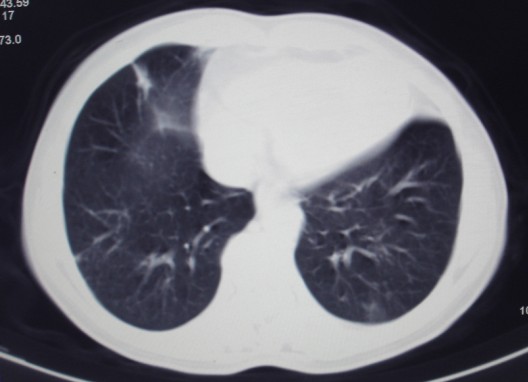

女,60岁咳嗽咳痰7天,痰中带血,有发热史,血象大约6000

双肺多发病灶,呈多形性,多叶分布,左上叶尖后段靠胸壁病灶伴有空洞,边缘模糊,与胸壁呈刀切征.

考虑混合感染以tb为主.

多灶,多形,少聚,少块。卫星灶,空洞影,树芽征,结核可能性大